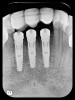

Six months later, the periodontist prepared osteotomies and placed three 3.25-mm x 13-mm implants using a vacuum-formed surgical guide fabricated by the restorative dentist (using a cast of the provisional bridge as a guide, as described by Block et al16); healing abutments were placed simultaneously. A post-implant radiograph confirmed good implant alignment with the pontics of the provisional from teeth Nos. 22 through 28 (Figure 6).

Figure 6  Confirmed ideal implant alignment with pontics in provisional bridge from Nos. 22 through 28—post-placement periapical view.

Figure 6

Figure 9: Implants supporting zirconia abutments and crowns, site Nos. 24 through 26—periapical view.

Figure 9